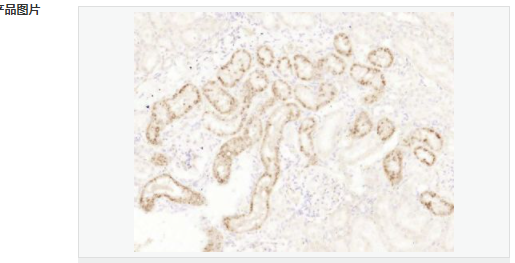

| 產(chǎn)品應(yīng)用 | ELISA=1:5000-10000 IHC-P=1:100-500 IHC-F=1:100-500 ICC=1:100-500 IF=1:100-500 (石蠟切片需做抗原修復(fù)) not yet tested in other applications. optimal dilutions/concentrations should be determined by the end user. |

| 產(chǎn)品介紹 | This gene encodes a member of the latrophilin subfamily of G-protein coupled receptors (GPCR). Latrophilins may function in both cell adhesion and signal transduction. In experiments with non-human species, endogenous proteolytic cleavage within a cysteine-rich GPS (G-protein-coupled-receptor proteolysis site) domain resulted in two subunits (a large extracellular N-terminal cell adhesion subunit and a subunit with substantial similarity to the secretin/calcitonin family of GPCRs) being non-covalently bound at the cell membrane. Latrophilin-1 has been shown to recruit the neurotoxin from black widow spider venom, alpha-latrotoxin, to the synapse plasma membrane. Alternative splicing results in multiple variants encoding distinct isoforms.[provided by RefSeq, Oct 2008] Function: Calcium-independent receptor of high affinity for alpha-latrotoxin, an excitatory neurotoxin present in black widow spider venom which triggers massive exocytosis from neurons and neuroendocrine cells. Receptor for TENM2 that mediates heterophilic synaptic cell-cell contact and postsynaptic specialization. Receptor propably implicated in the regulation of exocytosis. Subcellular Location: Cell membrane. Cell projection; axon. Cell projection; growth cone. Cell junction; synapse. Cell junction; synapse; presynaptic cell membrane. Cell junction; synapse; synaptosome. Colocalizes with TENM2 on the cell surface, across intercellular junctions and on nerve terminals near synaptic clefts. Post-translational modifications: Autoproteolytically cleaved into 2 subunits, an extracellular subunit and a seven-transmembrane subunit. This proteolytic processing takes place early in the biosynthetic pathway, either in the endoplasmic reticulum or in the early compartment of the Golgi apparatus. Similarity: Belongs to the G-protein coupled receptor 2 family. LN-TM7 subfamily. Contains 1 GPS domain. Contains 1 olfactomedin-like domain. Contains 1 SUEL-type lectin domain. SWISS: O94910 Gene ID: 22859 Database links: Entrez Gene: 22859 Human Entrez Gene: 330814 Mouse SwissProt: O94910 Human SwissProt: Q80TR1 Mouse Unigene: 94229 Human Unigene: 260733 Mouse Unigene: 10776 Rat Important Note: This product as supplied is intended for research use only, not for use in human, therapeutic or diagnostic applications |